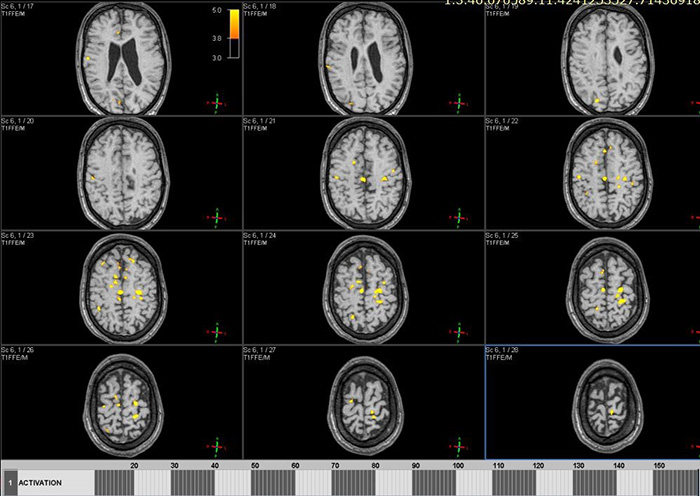

Цель: Апробация и внедрение в клиническую практику современных методик фМРТ и DTI для оценки структурных и функциональных изменений при нарушениях движения у детей. Описание проекта: Для Детского Церебрального Паралича характерно наличие незначительных структурных повреждений [1], при этом неясна их связь с нарушениями двигательных функций. фМРТ позволяет выявить зоны активации мозга при выполнении движений и оценить сложность выполнения задания по объему зон активации (Рис 1). МР-трактография позволяет исследовать структуру и диффузионные характеристики проводящих путей мозга (Рис 2). МР-волюметрия также позволяет оценить объем основных структур мозга и выявить аномалии развития, кортикальные дисплазии и патологии белого вещества мозга (Рис 3.). Результаты: Проведена клиническая апробация предложенных методик. Результаты представлены на медицинских неврологических конгрессах.

Рис 2.А.– автоматическая сегментация и рассчет объемов структур мозга по данным МРТ позволяет локализовать и оценить повреждения белого и серого вещества мозга.